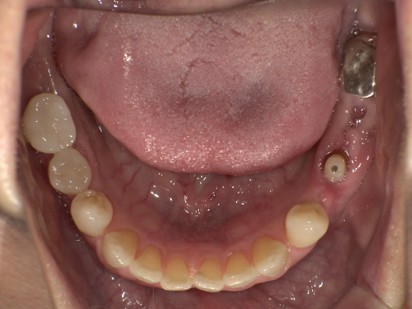

治療前

| 主訴 |

上の左右の奥歯がないのでインプラントについて相談したい。 |

| 治療内容 |

上の奥歯に4本のインプラントを埋入する計画を立てました。 右上は骨の厚みが足りないためCGF(骨再生材料)を用いてソケットリフト(副鼻腔の粘膜も持ち上げて骨の高さを作る処置)を行いインプラントを埋入しました。左上5番は歯根破折のため抜歯して即時に2本インプラントを埋入しました。ご本人の希望で上記処置を1日で行いました。1時間30分程度の時間を要しましたが、ご本人の頑張りもあって無事手術を終える事ができました。 4カ月経過後にインプラントと骨が適切に付着しているか確認し、ジルコニアの上部構造を装着しました。 |